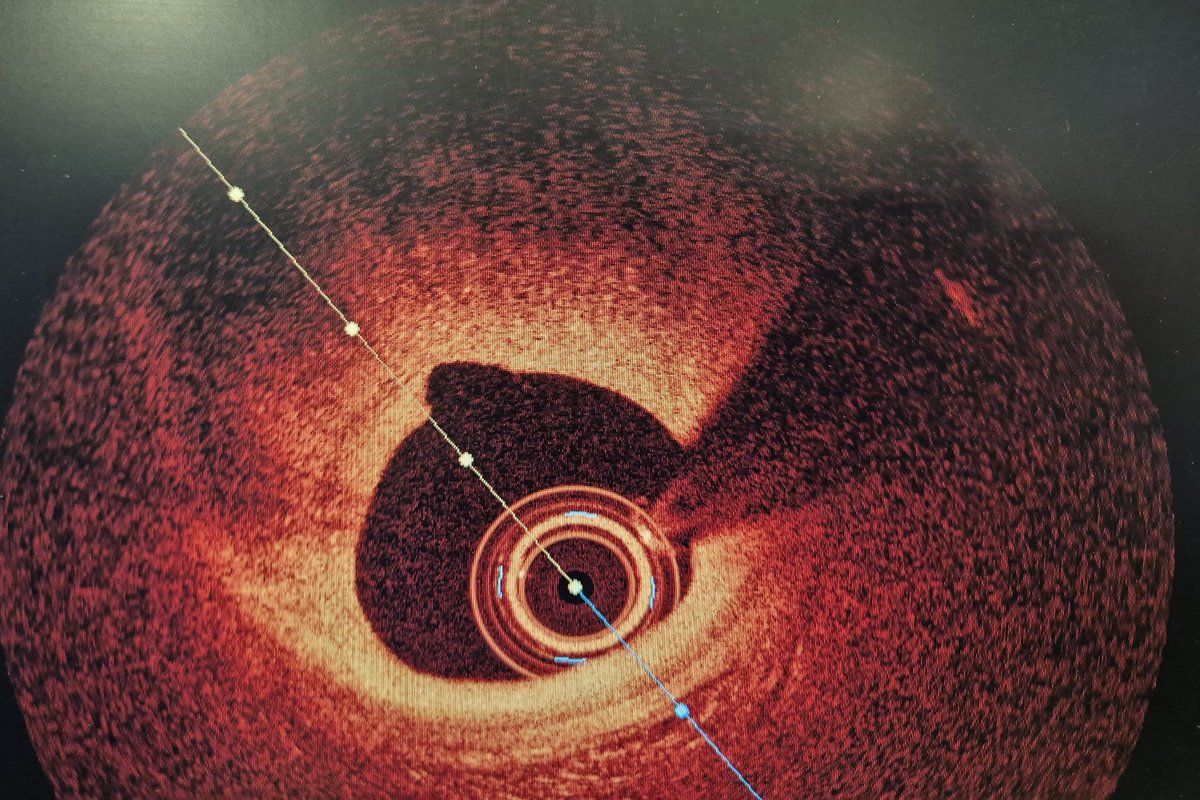

A 63 y.o female presented with NSTEMI. One year before CTA with normal LAD/RCA and mild lesion in OM1. Here is the angio and OCT images. What would you do?